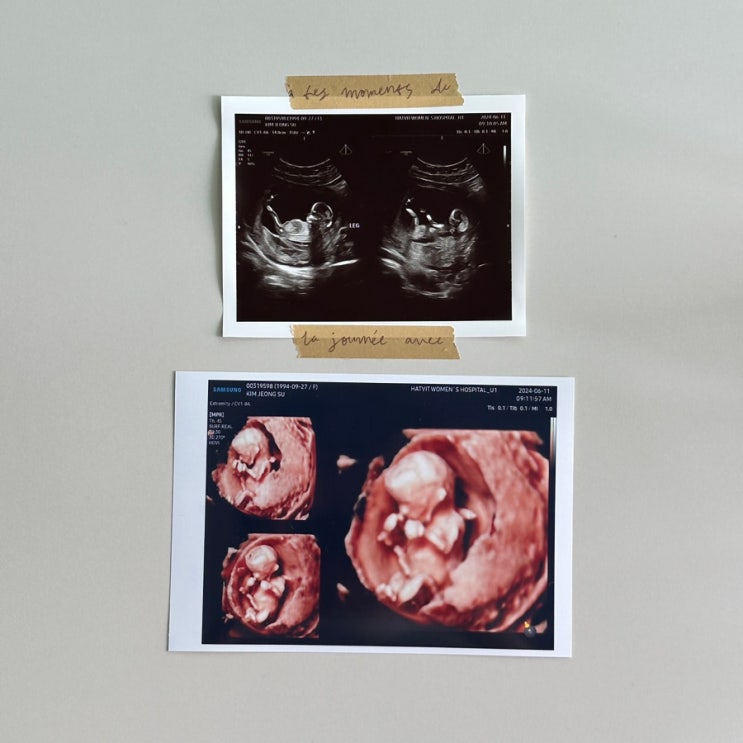

임신일기 (5) 12주차 첫 정밀초음파, 1차 기형아검사 | 팔 다리가 길어진 수수

임신일기 (5) 12w6d 1차 기형아 검사 팔 다리가 길어진 수수 12주 6일차 2주만에 찾은 병원! 12주차는 첫 ...